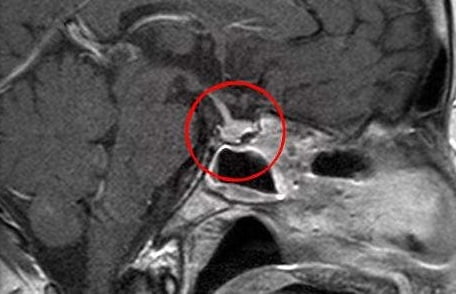

- проведение МРТ или КТ (визуализация эндокринной железы);

Диагностика аденомы гипофиза обычно включает в себя клинический осмотр, анализы крови на уровень гормонов и визуализирующие исследования, такие как магнитно-резонансная томография (МРТ), которая помогает определить размер и расположение опухоли.